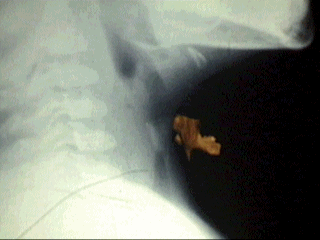

PACTE.7 A�OS DE EDAD QUE

PRESENTO ESTRIDOR DE CAR�CTER BRUSCO Y DISFONIA DE 2 DIAS DE

EVOLUCION TRATADO COMO STATUS ASMATICO. EN Rxs. SE OBSERVA CUERPO

EXTRA�O ALOJADO EN SUBGLOTIS

FOREIGN BODY IN LARYNX .